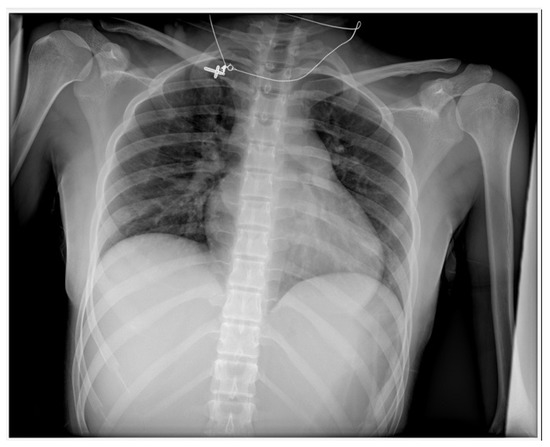

Case Report